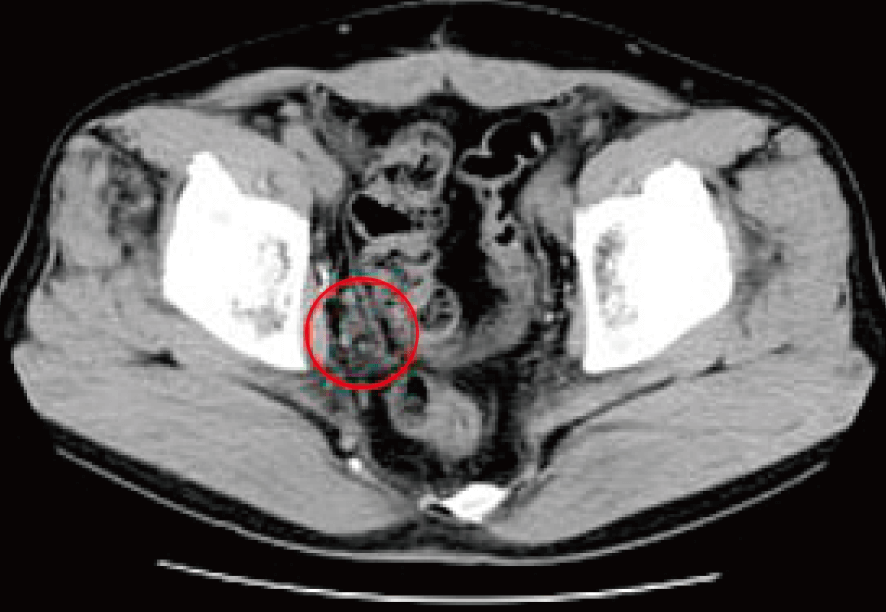

治療前CTでは骨盤底部、右側(写真では左・赤マル部分)に、リンパ節転移として腫れたがん病巣が数個認められた。

提示した下腹部CT写真は治療終了後およそ3カ月経過時点のもの。

治療前に存在していた骨盤内のリンパ節転移もほぼ消滅していた。